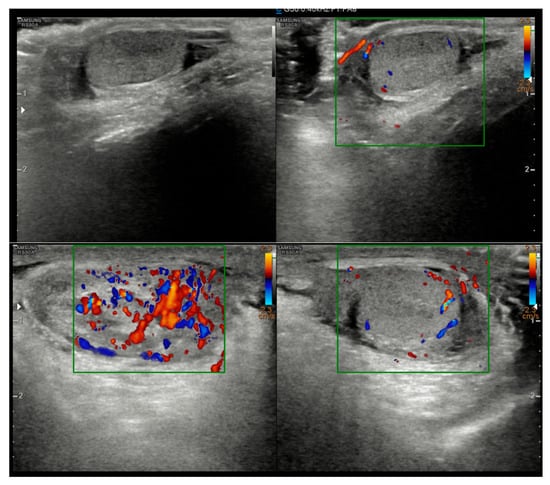

A 5-year-old boy, born in Catania, Sicily, Italy, to a Sri Lankan migrant family, was evaluated for left testicular pain and swelling. He had no prior hospitalizations or significant medical history. He was fully vaccinated. The symptoms were initially attributed to orchiepididymitis, as the left testis was edematous, painful, and hyperemic. The patient was treated with oral amoxicillin/clavulanate and nonsteroidal anti-inflammatory drugs (NSAIDs) for 10 days. There was mild improvement in swelling, but testicular pain persisted. Laboratory tests, including blood counts and inflammatory markers, showed only mild thrombocytosis (415,000/mmc). An ultrasound performed at the Pediatric Emergency Department of Garibaldi Nesima Hospital in Catania showed thickening of the left spermatic cord with increased blood flow on Doppler, while the testes appeared normal in morphology, and no hydrocele was present (Figure 1). Two weeks later, at a follow-up visit, the boy’s symptoms had worsened. A firm, elastic, mobile mass was palpated in the left inguinal/scrotal area, distinct from the right testis. The testis ultrasound at that time revealed a well-defined, round hypoechoic mass (measuring 8.5 mm) with linear hyperechoic structures within it (Figure 2).

Figure 1.

Initial ultrasound showing a thickened left spermatic cord with increased vascular signals.

The inflammatory reaction seen in this patient is a characteristic feature of these infections and is often linked to the host’s immune response against a dying or degenerating worm, which can lead to the release of worm antigens or symbiotic Wolbachia bacteria [16]. In our case, we did not identify Wolbachia antigens. Imaging played a key role in guiding the diagnosis. While initial ultrasound findings were non-specific, the follow-up imaging revealed a nodule containing linear hyperechogenic structures. Although worm motility was not observed, this “worm-in-a-bag” sign is highly suggestive of an encysted helminth [17]. Awareness of these sonographic features is critical for clinicians to distinguish these lesions from tumors, as misdiagnosis has previously led to unnecessary orchiectomies [6,18].